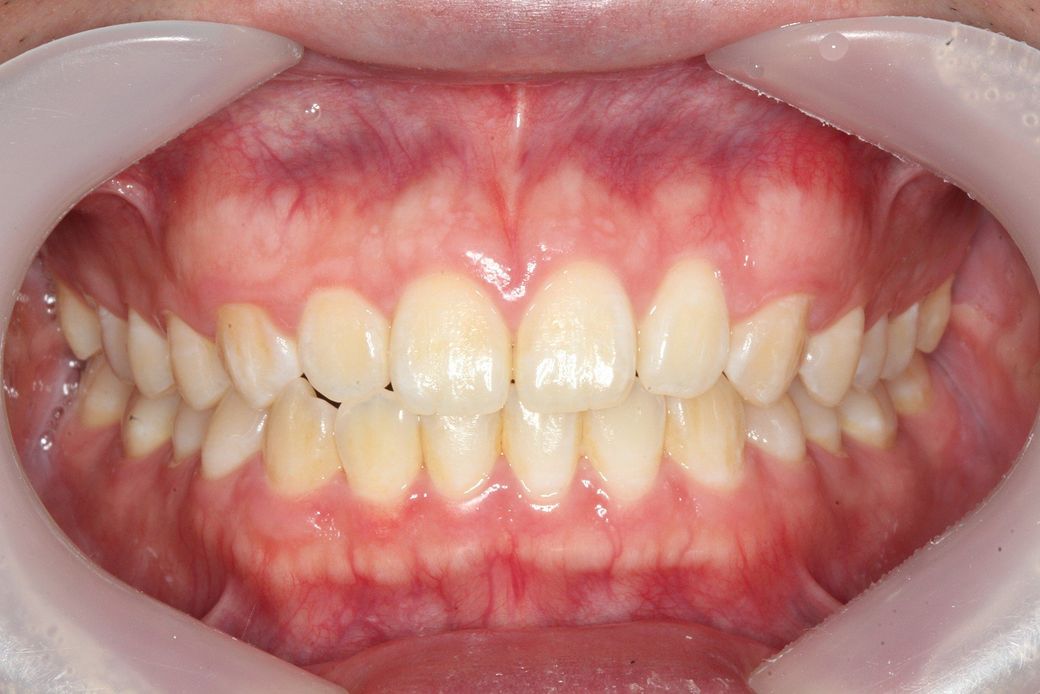

• 3번 째 사진

일전에도 문의주신 것으로 기억합니다. 현재 좌측으로 canting 되어 있으나 이는 사람에 따라서는 치료의 대상이 아닐 수도 있습니다. 모든 사람은 양쪽으로 모두 대칭인 수평인 경우는 거의 없으며 한쪽으로 canting되어 있는 경우가 많습니다. 이때 canting 범위에 따라 정상일 수도 있고 정상이 아닐 수도 있으나 이는 본인이 심미적으로 전혀 문제가 되지 않는다고 본다면 치료를 하지 않아도 됩니다.

현재 교합이 완전하다고 할 수는 없습니다. 따라서 교정적인 힘으로 치열을 바꿀 수는 있어 보여도 상당히 어려운 과정을 거쳐야할 것으로 보이며 교정 전 후가 크게 달라지지 않을 수 있어 보입니다. 발치 교정도 현재로서는 애매하고 비발치 교정에도 한계가 있어 보입니다. 즉 정상범주에서 특별히 많이 벗어나는 것이 아니라는 것입니다.